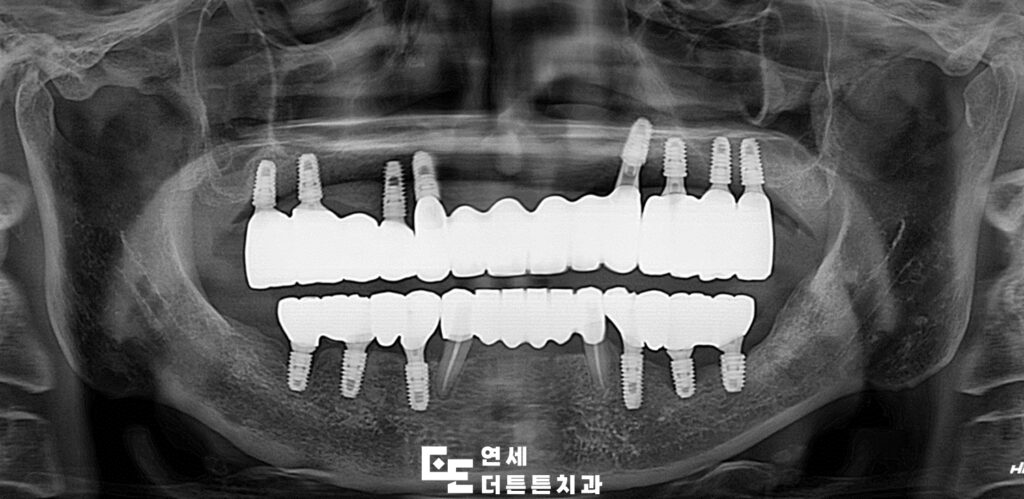

따라서, 살려 쓸 수 있는 치아 2개 정도를

제외하고 모두 발치 후 망월사역치과 전체임플란트를

진행하시기로 하였습니다.

양쪽 아래 송곳니 두 개는

신경치료 후 크라운을 진행하고

나머지는 모두 임플란트를 진행하였습니다.